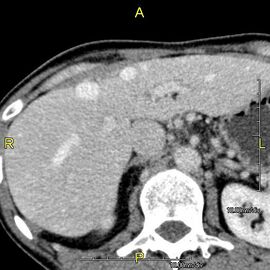

-

صورة مقطعية محورية تظهر أوردة كبدية شاذة تنتشر على السطح الأمامي تحت المحفظة للكبد.[73]

صورة مقطعية محوسبة بإسقاط الشدة القصوى (MIP) كما تبدو من الأمام تظهر الأوردة الكبدية الشاذة التي تمتد على السطح الأمامي للكبد.

منظر جانبي بإسقاط الشدة القصوى لنفس المريض كما في الصورة السابقة.

فحص بالتصوير المقطعي المحوسب يظهر فيه الكبد والوريد البابي.